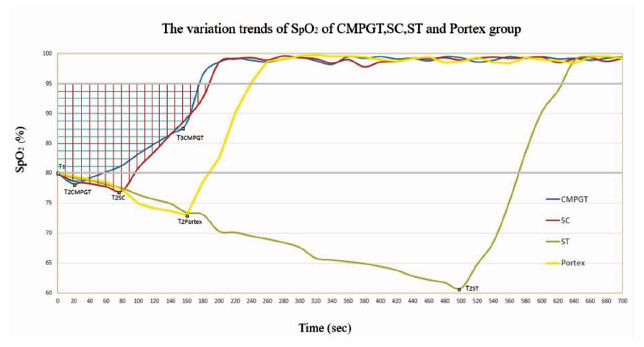

2 结果 2.1 时效性所有小型猪(20/20)均成功建立气道并通气。四组小型猪术后的心电监控和动脉血气指标并没有显著的组间差异,但是每组可见显著的术前和术后差异(P<0.05),表明四种方法均可以有效的恢复通气和供氧(图 1A)。ECG显示停止供氧后T波降低、QT间期缩短,可能与心率变化、交感神经过度活跃和心肌缺氧有关。SC、GWDF、CMPGT和ST的手术时间分别为(86±12)s,(165±63)s,(174±34)s和(519±128)s,但是CMPGT恢复通气的时间最短,为(23±4)s (P<0.01) (图 1)。这是因为一旦穿刺管通过环甲膜进入气管,既可以通过气囊打气供氧,而非像其他3种方法必须要插管后才能恢复通气。四组的SpO2从T2开始快速上升,并分别于(176±28)s(CMPGT),(189±17)s(SC),(240±43)s(GWDF)和(628±117)s(ST)时达到95%(图 1B)。CMPGT、SC、GWDF和ST组SpO2曲线的上升部分斜率分别为0.11、0.17、0.29和0.3,说明GWDF和ST组在建立气道插管后的通气能力要强于SC和CMPGT。但是需要注意的是CMPGT包括两个阶段的两种不同的通气方式,第一阶段通过穿刺管上的气孔通气(T2至T3),此时SpO2曲线的斜率为0.07;第二阶段通过气管造口处插管(T3至T4),SpO2曲线的斜率为2.75。由于穿刺管的直径较细(内径4 mm),通过穿刺管上气孔的通气能力不如气管造口后插管,但仍可以提供足够的通气,以便尽快的解除缺氧。CMPGT组的SpO2曲线和95% SpO2线间的面积最小(与GWDF和ST组相比P<0.01;与SC组相比P<0.05),说明CMPGT是四种方法里最具有时效性的手段(图 2)。小型猪的皮肤至气管的距离约为3~4 cm,人类一般为2 cm左右,同时小型猪皮肤质地更为坚韧,因此可以合理的推测将CMPGT用于患者时可能操作时间更短。

| 图 2 四组的SpO2变化曲线 Fig 2 Change of SpO2 in the four groups |